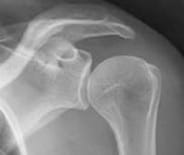

In the normal shoulder (glenohumeral joint), motion occurs across smooth surfaces lined with cartilage. As seen on the X-ray to the right, the normal shoulder has smooth surfaces lined with cartilage that cushions the impact between the bones and provides a smooth gliding surface for movement.